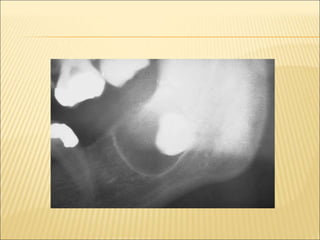

Radiographic Features

 Unilocular ,well defined radiolucency with

sclerotic margins around the crown of an

unerupted tooth

 Three radiographic types

circumferential

lateral

paradental